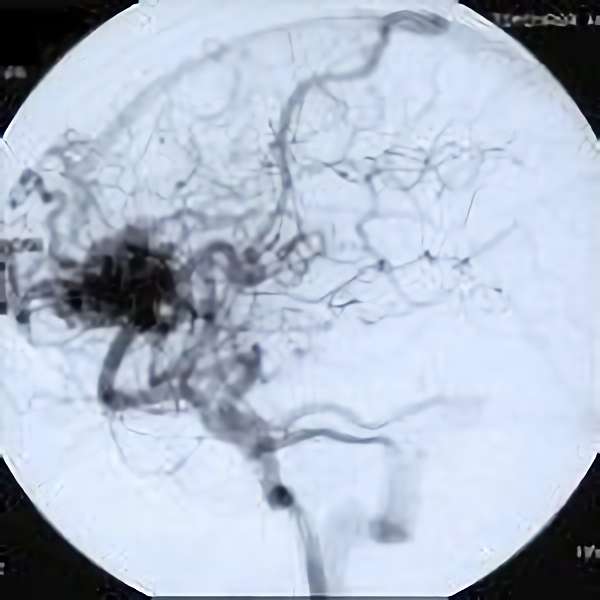

'19年5月

30代

富永/久貝

右中小脳脚 出血再発

SM 3(S1,E1,V1)

米国の病院

No.359 モニタリング

No.359 手術前

No.359 手術中

No.359 手術後

出血既往があり。2回の手術前血管内手術の後に、

Lateral transpeduncular approachにより再々出血予防を目的に

摘出手術を行う。完全摘出であることを確認した。

手術による合併症や後遺症なしで退院した。経過良好。